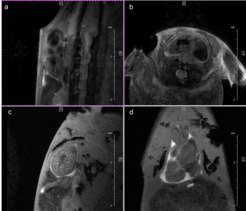

Fig. 2: Mouse heart MRI. In the upper panel the endsystolic (a) and enddiastolic (b) phase of a mouse heart in the 4-chamber-view is displayed. In red: position of the 7 slices, orthogonal to the septum (1.0 mm thick, no gap). In the lower panel in (c) the endsystolic and in (d) the enddiastolic phase of an axial midventricular slice is shown. Note the papillary muscle.

This is also due to the fact, that we use retrospective gating technique: Cardiac and respiratory cycles are detected by a navigator signal, and therefore no triggering hardware is required. The so-called “self-gating” IntragateTM Tool (Bruker BioSpin, Ettlingen, Germany) provides a steady state condition which avoids the flashing effects common to conventional ECG triggering and respiratory gating. Especially for our newt the renouncement of electrodes fixated on the tiny legs is much more comfortable for animal and investigator. The self-gating method of Intragate additionally uses intrinsically a kind of segmentation – several echoes during one heart cycle are utilized for the same image – significantly reducing the measurement time for the same SNR compared with the classical methods triggered by the ECG-signal (Fig. 3).

Fig. 3: Newt heart MRI. In the upper panel two localizer scans (RARE method (rapid acquisition with relaxation enhancement) with a repetition time of 2500 ms, echo time of 36.7 ms, slice thickness/interslice distance: 0.50/0.50 mm, field of view 2.50x2.50 cm2 and a matrix of 256/256 (a)) are shown: two 2-chamber views (a,b). In the lower panel an image of the ventricle in axial (c) and coronal (d) orientation is presented. We imaged the animal with an Intragate Flash (Fast Low Angle Shot) sequence: repetition time: 5.6 ms; echo time: 2.9 ms; oversampling: 150 (c) or 300 (d); flip angle: 10 deg; slice thickness/interslice distance: 0.3/0.3 mm; FOV: 15x15 mm and matrix: 256/256 (c) or 128/128 (d) using the 72 mm volume transmit-only room temperature and the cryogenic 4 element 1H array receive-only coil.